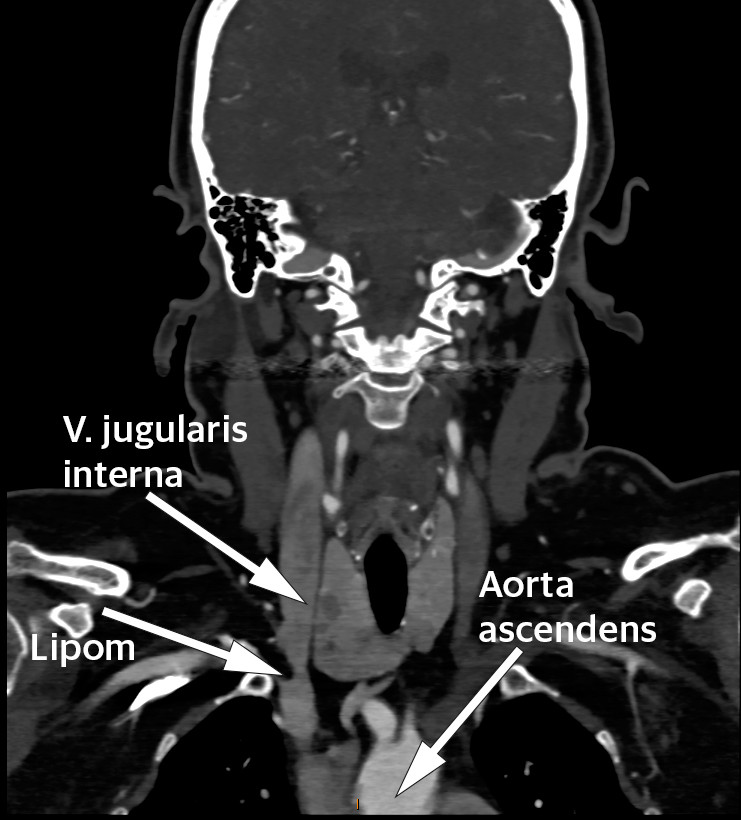

En kvinne i 60-årene med diabetes type 2 og hypertensjon ble utredet for mulig carotisstenose med CT-angiografi (kontrastforsterket CT). CT viste åpne arterier uten stenoser, men som et bifunn fant man en oppfylning i høyre vena brachiocephalica like etter konfluksen mellom vena subclavia og vena jugularis interna.

Oppfylningen målte 17 × 8 × 12 mm og hadde tetthet forenlig med fett (begge bilder). Det ble i tillegg gjort ultralyd og konkludert med at hun hadde et intravenøst lipom. Få tilfeller er beskrevet i litteraturen, de fleste lokalisert til vena cava inferior eller hjertet, men også beskrevet i vena brachiocephalica (1). Man kjenner ikke til i hvor stor grad intravenøse lipomer fører til venøs okklusjon, embolisering eller trombedanning (2). Enkelte anbefaler å fjerne lipomene, da kun histologisk undersøkelse kan skille mellom lipom og liposarkom (2, 3). Tross dette finner vi ikke ved søk i Pubmed at det er rapportert om intravenøse liposarkomer. Andre anbefaler kun å fjerne lipomene dersom de gir symptomer som følge av kompresjon eller smerte (4). Det synes som om mindre og asymptomatiske intravenøse lipomer kan observeres. For vår pasient er det derfor planlagt kontroll med MR om ett år.